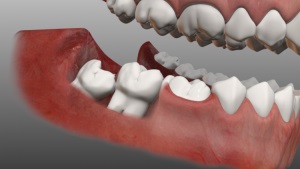

Ha egy egyszerű ember az utcán, amikor meglátogatja a fogorvos szembesül a fogalmak a „utópia” és a „visszatartás”, ezeket a kifejezéseket gyakran zavarba, ijedt és kénytelen keresni a választ, hogy mit jelent. A valóságban a dolgok nem olyan rossz. Mikor jön a disztópia, az azt jelenti, hogy a korona megfelelő található az állkapocs és nem növekszik a szempontból, megtörve a harmóniát a fogazat. Mikor jön a foga visszatartás, ami azt jelenti, hogy annak ellenére, hogy nőtt fel, de ne vágjuk át, és teljesen vagy részben található a gumik vagy a csontban az állkapocs.

Visszatartás egy teljes és részleges. Poluretinirovanny fogak azt jelenti, hogy a gumi látható csak a széle a koronát. Patológiai válthatnak mindenféle okok miatt. Például Vágóasztal arc mellett már nőtt a koronát, hogy leáll a növekedés a fiatal fül, és ő marad az állkapocs. A másik oka a megtartását a fog túl vastag íny, amely nem teszi lehetővé növeli a koronát, hogy kitörjön. A megjelenése hatással szemfogak lehet a jelenléte túl sok fogászati sac, amelyen keresztül korona nem lehet vágni.

Miért Impaktált bölcsességfogak gyakran?

A leggyengébb a fogazat tartják bölcsességfogak, vagy a „nyolc”. Az okok között a megtartását bölcsességfog - nincs korábbi koronát, ami felkészíti őket a kiutat. „Nyolc” van áttörni a csont, ami okozhat fogak megtartása. Okok hatással egység - egy ütközés szomszédos fogak, vagy helyhiány miatt, amit a korona elmerül az íny. Abban az esetben, a veszélyeztetettség, bölcsességfog orvos azt ajánlja, hogy eltávolítja.

A fejlesztés a bölcsességfog antiutópia megkönnyítette az a tény, hogy vannak „nyolc”, majd később vannak a legrosszabb helyzetben. Ezen kívül helyezve őket egyrészt azt nem szabályozza egy másik korona, ezért bölcsességfogak nőnek megfelelően.